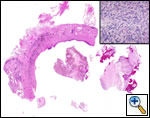

A standard lobectomy is performed. Dissection in the fissure is avoided as this will only lead to prolonged postoperative air leak. Instead, once the arterial anatomy has been defined, the fissures are completed with a stapling device. In rare instances the pulmonary parenchymal tissue is too thick to staple; in those cases, it must be taken with a clamp, cut, and then over sewn with chromic suture. A resected specimen is shown in Figure 5 along with the micrograph showing the typical appearance of recovered fungal elements (Figure 6).

![]() |

| Figure 5: A resected specimen | Figure 6: Appearance of recovered fungal elements |